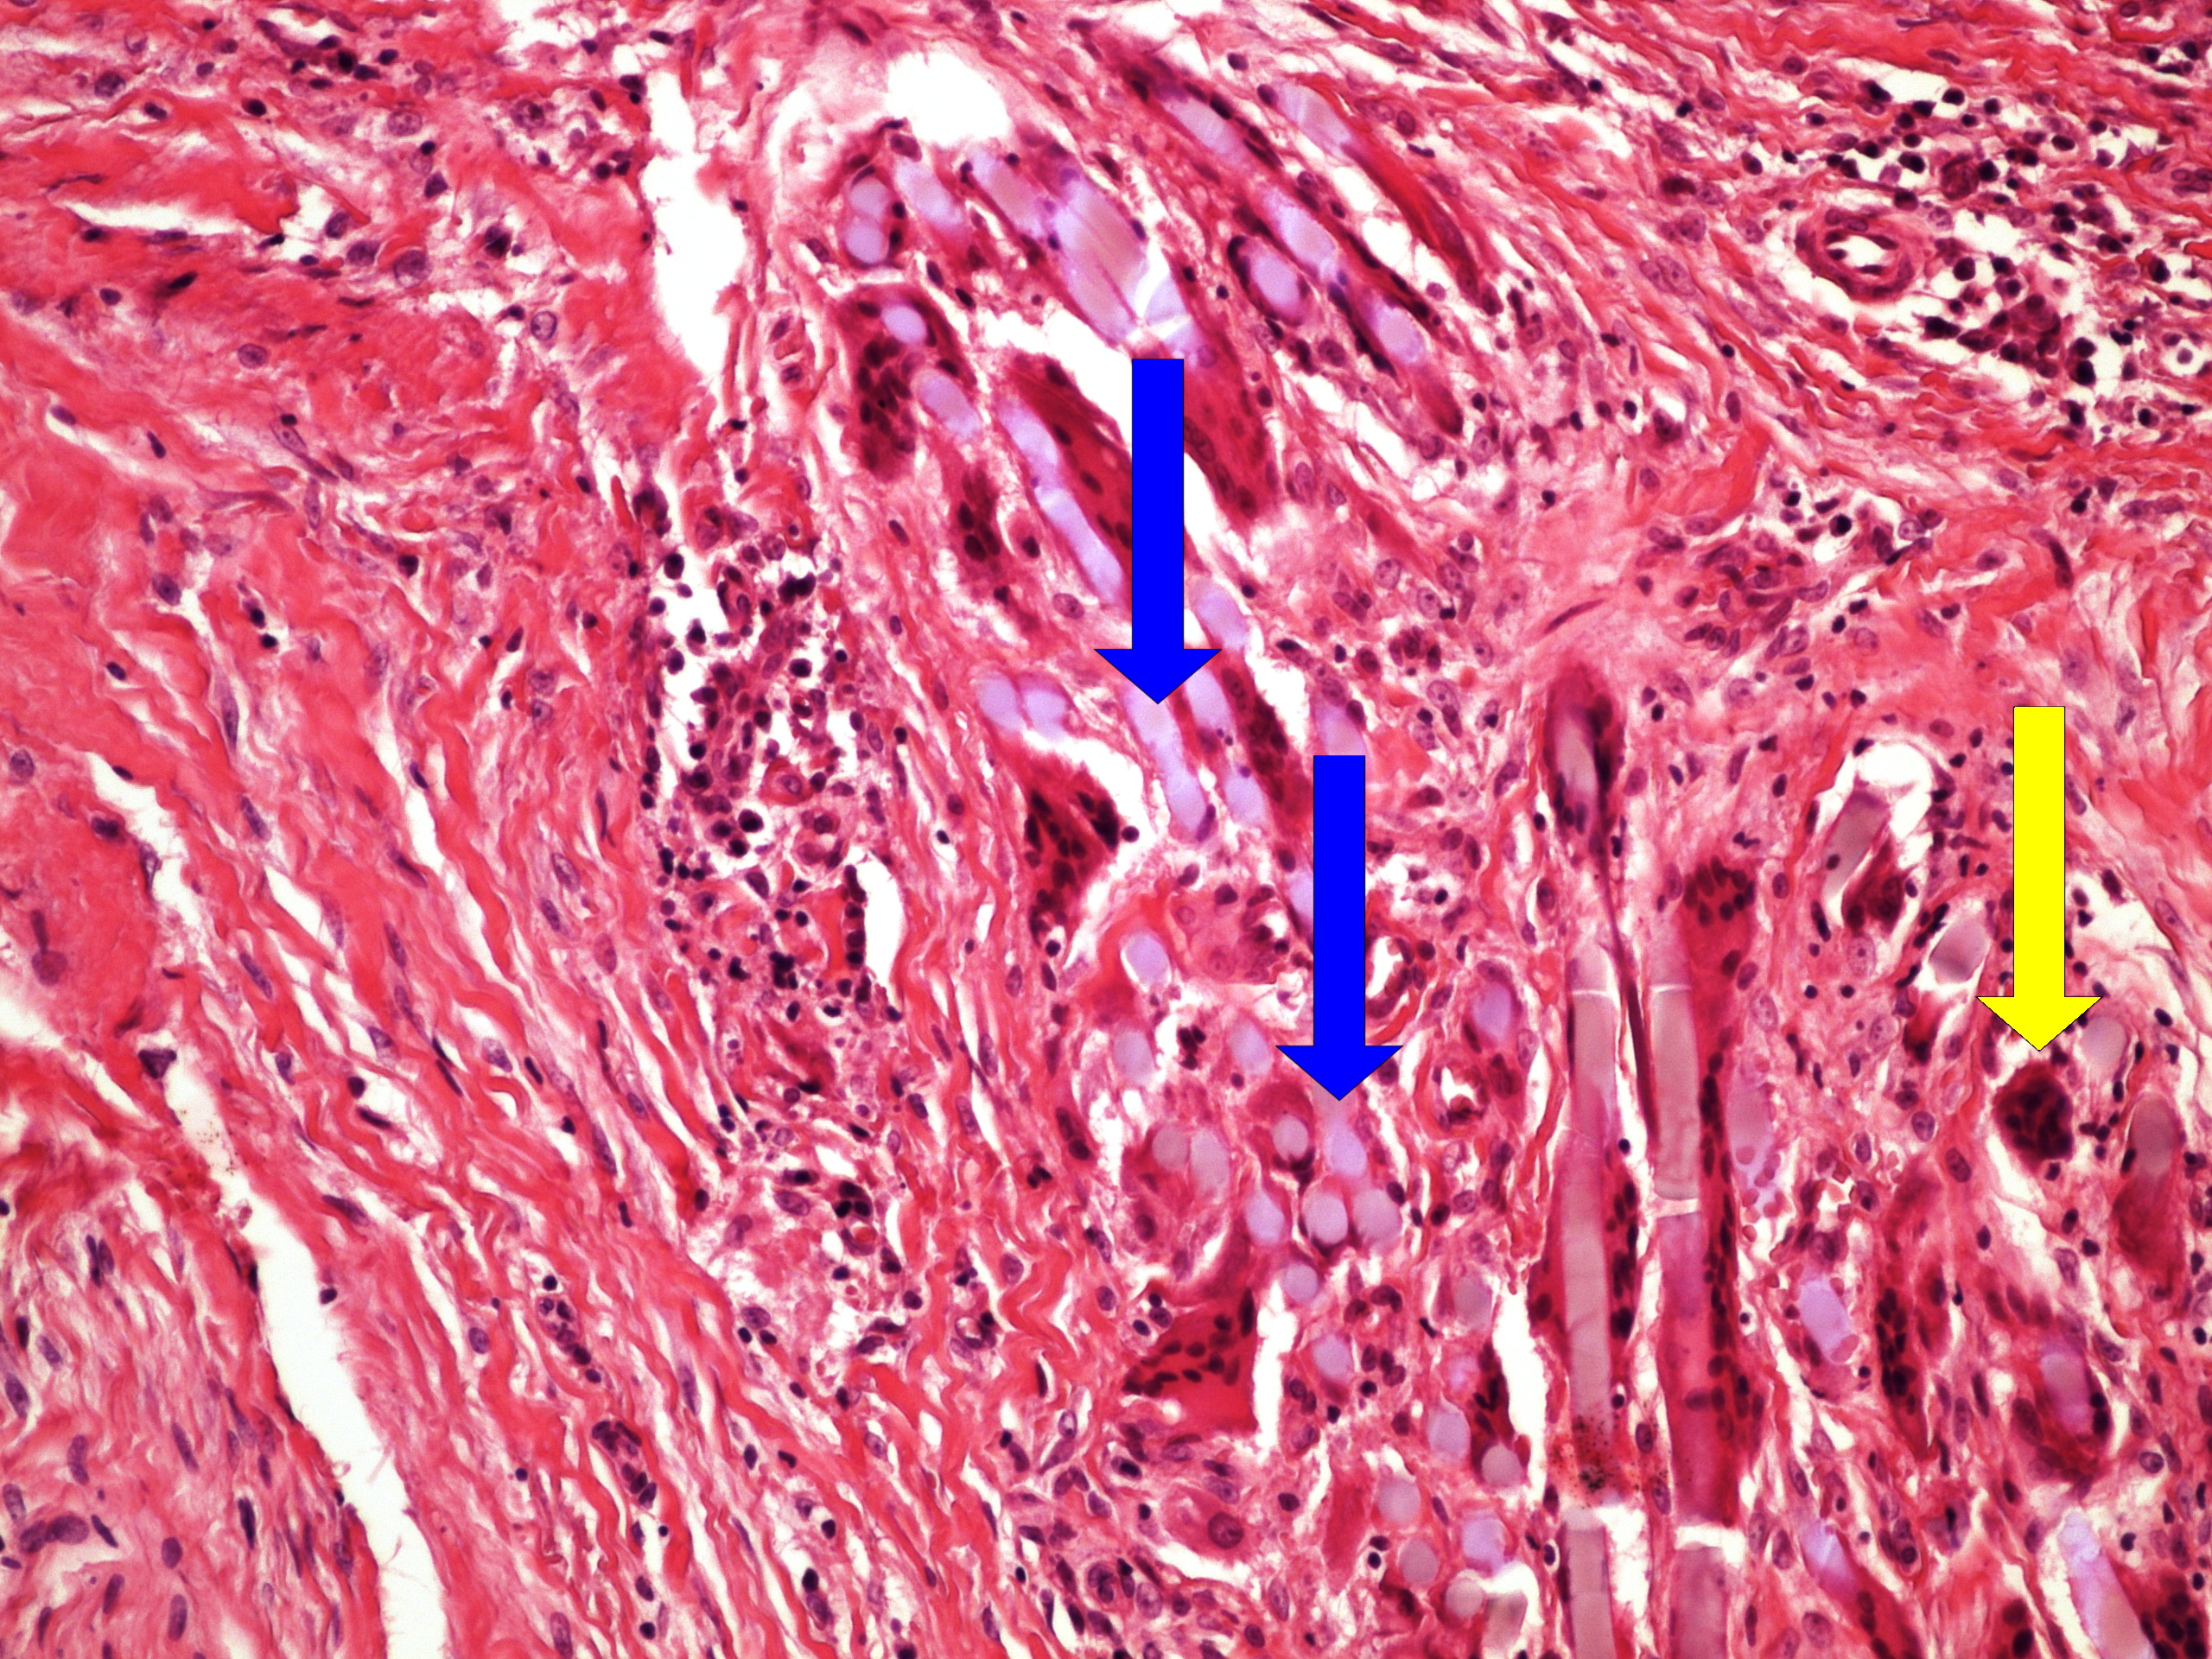

Preparát č.27 a č.28 - kaseózní pneumonie

Struktury

- kaseózní nekróza

- zbytek plicního parenchymu